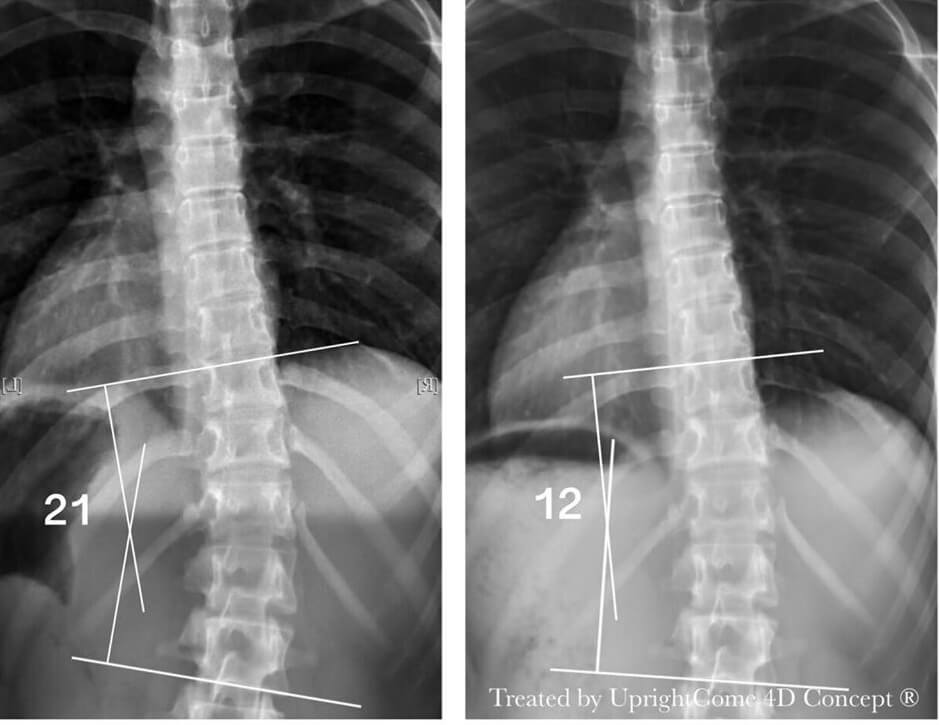

Case 12, 16 years, 21° Cobb

![脊椎側彎患者經過側彎矯正治療後,胸椎側彎角度由21度減少到12度。]()